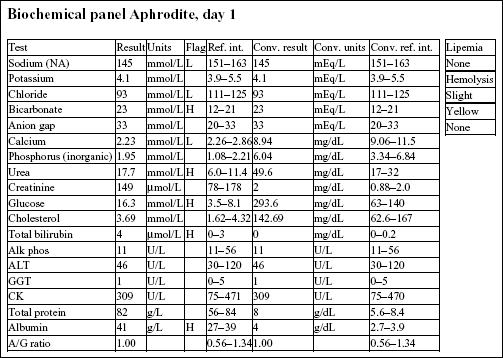

Aphrodite, a 4-year-old F(s) DLH cat, had anorexia, lethargy, and vomiting for 4 days.

The Hct and Hgb are mildly elevated and the RBC count is high normal. Total protein on the biochemical panel is high normal and there is a mild hyperalbuminemia. Total protein (solids), as measured by refractometry on the CBC, is less accurate than the biochemical determination. These findings, together with the history, suggest that the erythrocytosis is relative and due to dehydration.

There is a very mild leukocytosis, which is due to moderately increased band neutrophils and a mild monocytosis. The toxic change indicates accelerated release of neutrophils from the bone marrow. There is a significant inflammatory process, which may warrant follow-up CBC to determine if the bone marrow can continue to meet the demand for neutrophils.

Platelets often clump in feline blood samples; however, numbers are likely to be adequate in this case.

Decreases in sodium and chloride may be due to both decreased intake (anorexia) and increased losses (intestinal). However, chloride is also low relative to sodium, indicating selective chloride loss that can occur with gastric or duodenal foreign body, tumor, or swelling and inflammation leading to obstruction, or with gastrinoma (rare). The hypochloremic metabolic alkalosis also supports upper intestinal pathology. The mild hypocalcemia may not be significant. Mild urea elevation could be due to decreased renal perfusion or intestinal bleeding. Urinalysis would be required to assess renal function. Mild hyperglycemia is likely due to stress in this cat. Very mild hyperbilirubinemia may be secondary to bile stasis from anorexia or sepsis.

The CBC from day 3 is within reference limits. The absolute erythrocytosis and the inflammation were corrected with conservative therapy. Although a foreign body was suspected initially, Aphrodite recovered completely without surgical intervention.